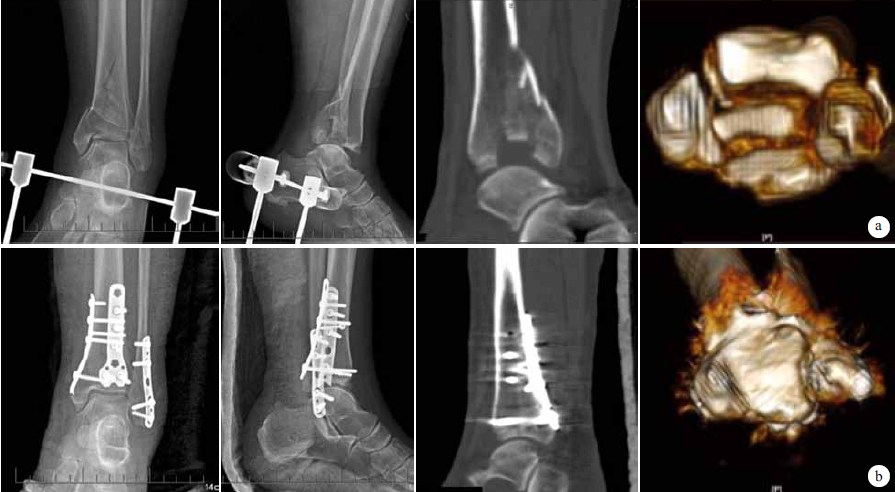

术后患者切口均Ⅰ期愈合。2例出现胫神经麻痹症状,口服弥可保营养神经药物后症状消失。12例获随访,随访时间12~18个月,平均14.5个月。术后3d依据Burwell-Charnley影像学评价标准判定骨折复位质量,关节面获解剖复位11例,一般复位1例;无内固定物进入关节内。X线片复查示骨折均于术后3~6个月愈合,平均3.7个月。随访期间无内固定物松动、断裂等并发症发生。见图1。

图1 患者,女,68岁,交通事故伤致左胫骨后Pilon骨折 a术前X线片及CT示后踝骨折累及内踝,关节面塌陷明显 b术后3d X线片及CT示骨折获得解剖复位 c术后14个月X线片示骨折愈合良好,内固定物无松动及断裂 d术后14个月踝关节屈伸功能及下蹲功能